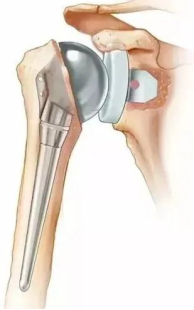

传统的肩关节置换术 反式人工肩关节置换术

反式全肩关节置换术是一种创新的手术方法,其设计原理与传统的肩关节置换不同,有独特的优势。具体是指人工肩关节头在上,盂在下,和正常人体肩关节头在下,盂在上的结构正好相反,所以又称为反式人工肩关节置换术。